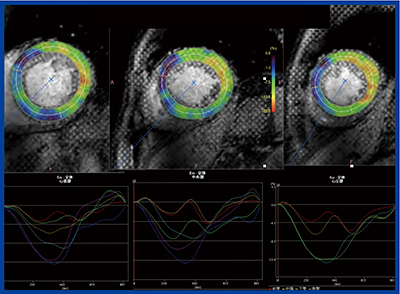

図5は拡張型心筋症のタギング画像と,心筋ストレインを心周期トレースしたグラフであるが,同期性障害がありストレインカーブのピークにズレが認められる。こうした症例の治療法の選択や予後の判断にdyssynchronyの評価はきわめて重要であり,それが自動で行えることは非常に大きなメリットがある。

図5 拡張型心筋症の心筋タギング法によるストレイン解析

〔LV dyssynchrony(+)〕